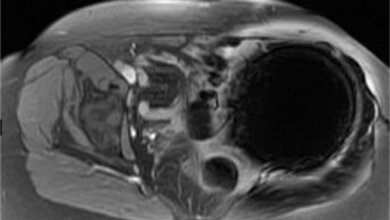

MRT zeigt Schäden in der weißen Gehirnmasse

Doch wie ein kanadisches Team nun herausfand, kann ein MRT hier wichtige Hinweise auf mögliche Entwicklungsschwierigkeiten geben. Das kanadische Team untersuchte in einem Zeitraum von sieben Jahren 58 Frühchen, die im British Columbia's Women Hospital mit Verletzungen in der weißen Gehirnsubstanz zur Welt kamen. Das Ziel der Studie war es, mit Hilfe der Magnetresonanztomographie (MRT) Schäden in der weißen Gehirnmasse quantitativ zu ermitteln und das Ausmaß und die Lokalisation der Schäden in Verbindung zu setzen mit den Entwicklungstadien der Frühchen bei 18 Monaten. Die Lage der Verletzungen wurde zunächst in der 32. Woche nach der Geburt ermittelt und die Kinder wurden erneut im Alter von 18 Monaten auf ihre geistigen und motorischen Fähigkeiten untersucht.

Die Deutsche Gesellschaft für Klinische Neurophysiologie und Funktionelle Bildgebung (DGKN) begrüßt den Einsatz bildgebender Verfahren, um die Gehirne von Frühgeborenen zu beurteilen. Mögliche Entwicklungsstörungen können so nicht nur früh erkannt, sondern auch gegebenenfalls behandelt werden. „Das MRT eignet sich hervorragend, um die Gehirne von Frühgeborenen auf Schäden zu untersuchen", erklärt Prof. Dr. Stefan Knecht, Chefarzt der Klinik für Neurologie der St. Mauritius Therapieklinik in Meerbusch. Während Röntgenstrahlen für Neugeborene schädlich sein können, sind die bildgebenden Magnetwellen eine harmlose Maßnahme. Hinzu kommt, dass das MRT wesentlich genauere Bilder liefert als es beispielsweise ein Ultraschall könnte. „Um auch die Langzeitfolgen der Schäden ausmachen zu können, müsste die Entwicklung der Frühgeborenen auch an weiteren Zeitpunkten während der frühen und späteren Kindheit beurteilt werden", ergänzt Knecht.